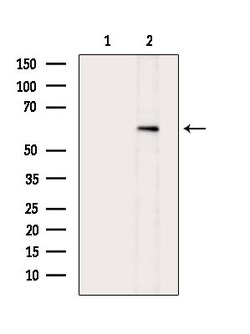

Invitrogen™ Phospho-AKT1 (Ser124) Polyclonal Antibody

Antibody detects endogenous levels of AKT1 only when phosphorylated at Ser124.

| Immunohistochemistry (Paraffin), Western Blot, Immunocytochemistry | |

| A synthesized peptide derived from human AKT1(Accession P31749), corresponding to amino acid residues around phosphorylated Ser124. | |